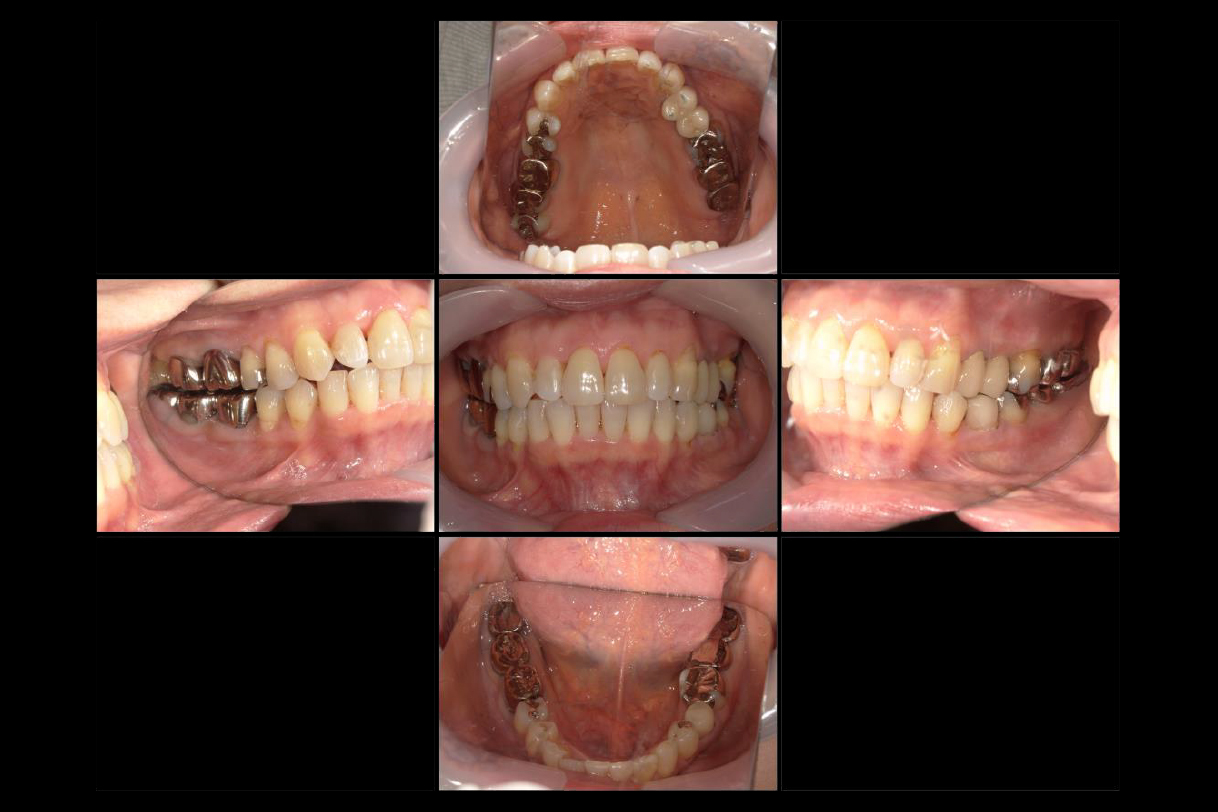

初診時年齢:40代男性

治療:全体矯正

治療法:マウスピース型矯正装置(インビザライン)

治療期間:3年

費用:902,000円(税込)

リスク・副作用:装置装着による違和感、歯の移動時の痛み